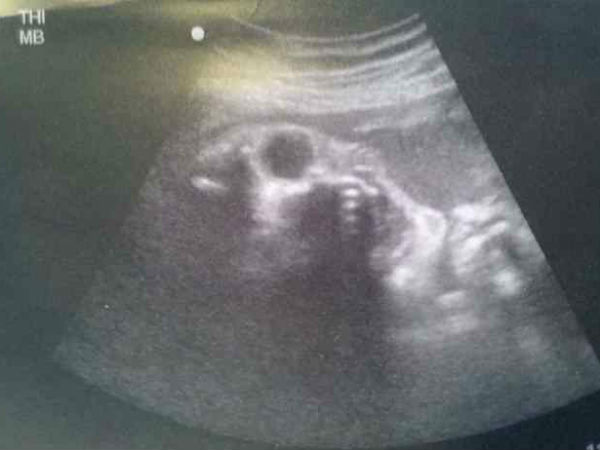

Scary Ultrasound Scans That Can Give You Goosebumps

When a woman realizes she is pregnant, she connects to the unborn child instantly. The span of waiting for the new member in the family seems to be the longest.

Amidst all the happiness around, when the woman goes in for her ultrasound, she would surely be nervous. But what happens if a little monster is captured during the scans?

Sounds scary, right? Here are some of the ultrasound images which will make you realize that even a tiny cute foetus can look really SCARY!

Picture# 1 The Alien Baby!

Does this child look exactly like an alien or is it a real alien baby? Well, the time would only reveal the real baby! We hope it comes in peace. Once the family realized the weirdness in the picture, it went viral!